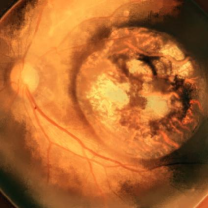

4.3 Style Transferring Neural Networks

Style transferring neural network in [16] was modified to generate new disease images. This network adopts layers from ”conv1 1” to ”conv4 1” in pre-trained VGG-19 [24] network for the encoder, whose weights are provided by ImageNet-pretrained weights. What’s more, multi-level stylization strategy proposed in [16] is applied to optimize the VGG features in different layers. Input images are three CFP images and three FA images as style images shown in Fig. 2 and 5. Six CFP images with three drusen and three GA images in Fig. 3 and Fig. 4. Also, FA images are applied to generate new images in Fig. 6 and Fig. 7. For CFP images, six images are shown in Fig. 3 and in Fig. 4. In Fig. 3, generated images contain round, discrete yellow-white dots, which are the symptom of drusen. In the same way, in Fig. 4, well-demarcated areas appear on the three images. Therefore, style transferring can generate new retinal symptom images.

Figure 4: Three CFP fundus images with symptom of GA and corresponding generated images. (a), (b), (c) Original images. (d), (e), (f) Generated images.